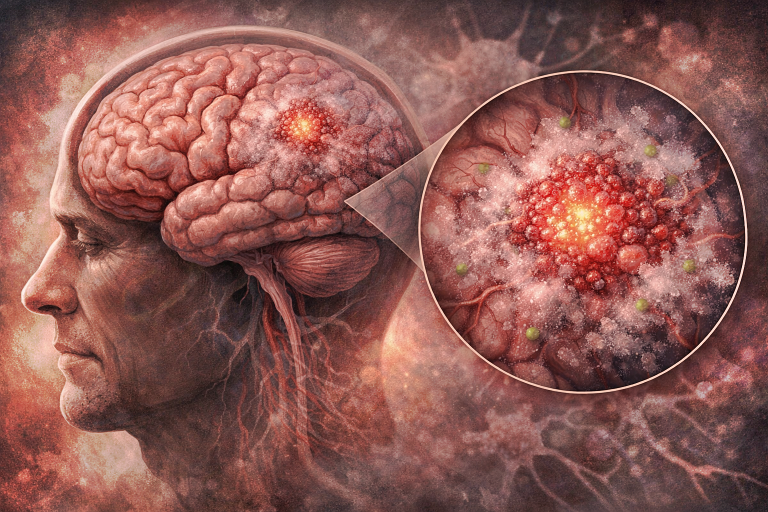

Limfoamele cerebrale sunt tumori maligne ale sistemului nervos central (SNC) care apar din celulele sistemului limfatic, în special limfocitele B. Ele reprezintă o formă rară de cancer cerebral și se pot manifesta ca limfom primar cerebral (în care tumora apare exclusiv la nivelul creierului și/sau măduvei spinării) sau ca limfom secundar cerebral (parte a unui limfom sistemic care s-a extins la creier).

5. Localizare anatomică

Limfoamele cerebrale apar frecvent în emisferele cerebrale, ganglionii bazali, corpul calos, talamus și periventricular.

Pot afecta de asemenea globii oculari (limfom ocular) sau lichidul cefalorahidian (infiltrare leptomeningeală).